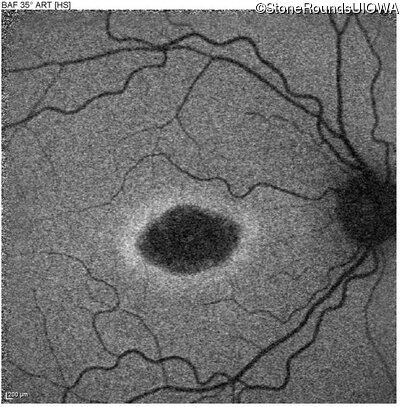

This 22 year old man had macular abnormalities noted incidentally at a routine eye exam at age 19. Since then, he has experienced a gradual loss of acuity particularly in the left eye.